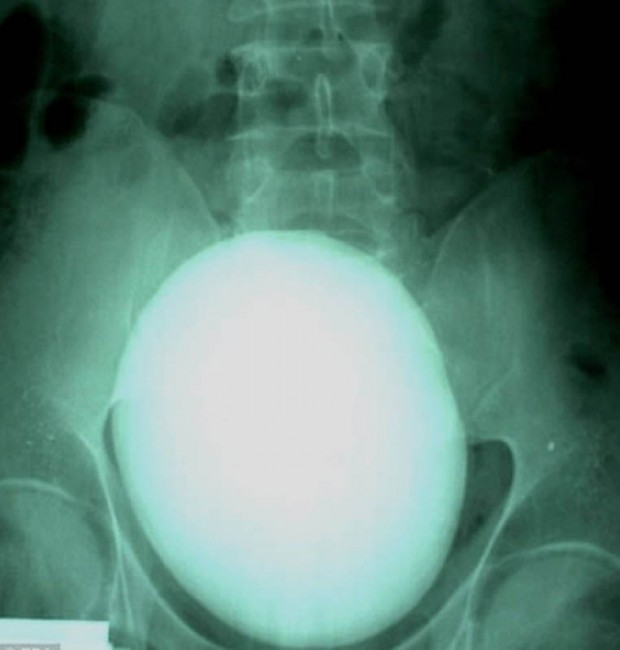

17. Вот такой вот 15-сантиметровый камень в почках весом 1,1 килограмм удалили пациенту из Венгрии.